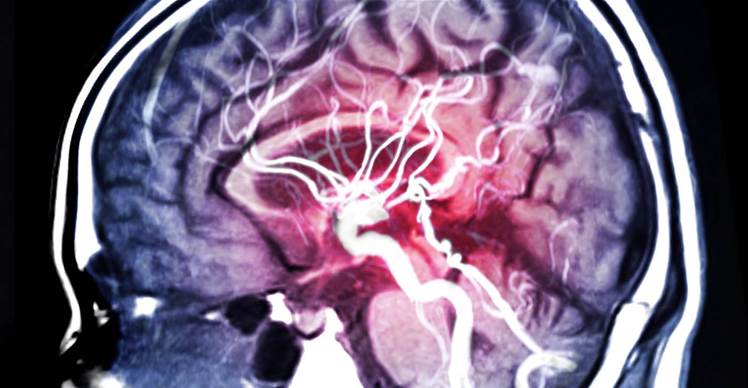

Brain aneurysms - weaknesses in blood vessels that can fill with blood and rupture - occur in up to eight percent of adults, but accurately and quickly identifying them on scans can be challenging.

One of the main outcomes of the project is to validate an AI algorithm that can highlight blood vessels that may have one or more aneurysms within an arterial ring at the base of the brain known as the ring of Willis.

Aneurysms are present in between two and eight per cent of adults, with multiple aneurysms in more than 10 percent of these people.

Rupture of an aneurysm causes brain haemorrhage in 85 percent of cases, leading to death in 30-40 percent of people and 20 percent permanent disability in those who survive.